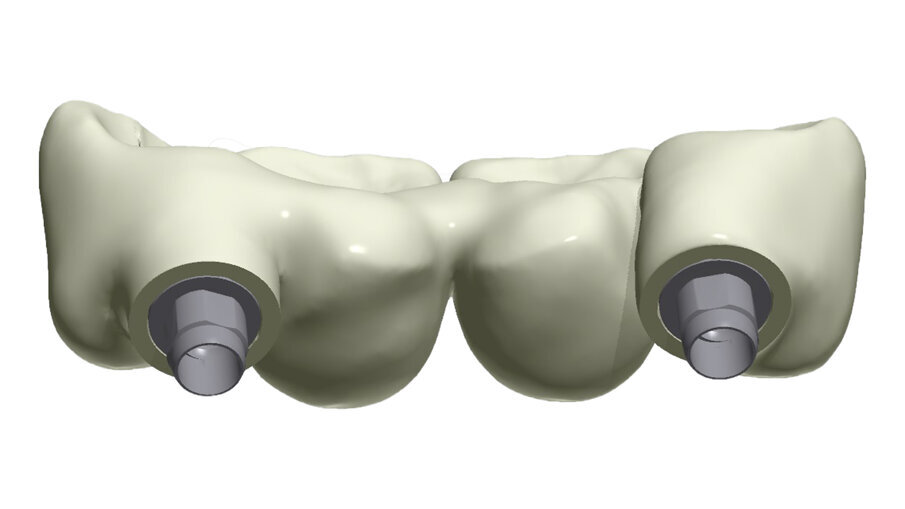

Gli impianti in Zirconia non offrono molte soluzioni protesiche, è importante che il loro posizionamento tenga conto di quest’aspetto mettendo l’odontotecnico nelle condizioni più favorevoli (Fig. 38). Questa sistematica prevede l’uso di un moncone in titanio cementato nella struttura protesica che permette l’avvitamento all’interno dell’impianto. Nella connessione implantare è presente un’intercapedine dove alloggia il collarino in titanio del T-base totalmente inglobato all’interno della zirconia, evitando comunicazioni coi tessuti adiacenti. Va comunque considerato l’aspetto tecnico importante legato allo spessore della struttura in zirconia che deve avvolgere l’intero moncone in titanio. (Fig. 39, 40).

Fig. 38_Il ponte tra gli impianti in Zirconia rappresenta un progetto complesso tra il rispetto del tunnel mucoso, l’anatomia vestibolare, gli spazi circolari e il foro per l’avvitamento coronale.

Fig. 39_Il progetto digitale consente all’odontotecnico di definire a livello circolare i limiti e gli spessori di rispetto della Zirconia.

Fig. 40_Anche la scelta dell’altezza del t-base è un’altra determinate al manufatto finale.